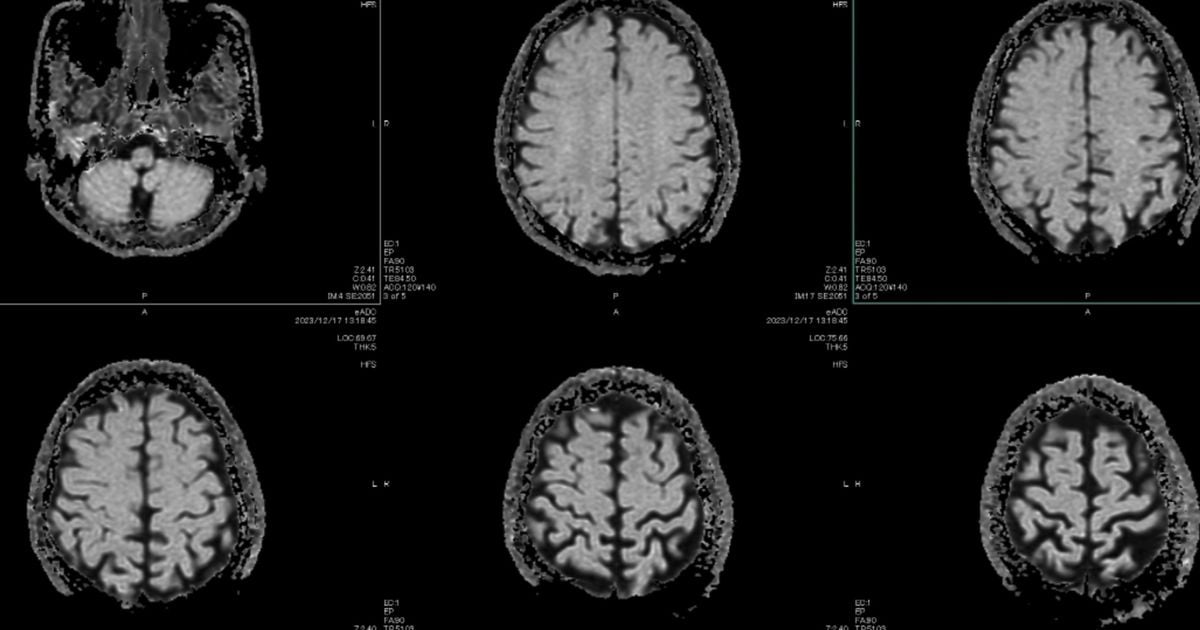

A principal teoria entre os cientistas que estudam o papel do cérebro na enxaqueca é que o ataque é uma onda elétrica lenta e anormal, que se espalha através do córtex cerebral, conhecida como depressão cortical alastrante (CSD, na sigla em inglês).

Esta onda suprime a atividade cerebral e faz disparar os nervos próximos que causam a dor, fazendo soar o alarme e gerando inflamações.

Em março de 2025, cientistas capturaram a onda em tempo real, enquanto monitoravam o cérebro de uma paciente de 32 anos, sendo preparada para cirurgia. Eles captaram a onda através de 95 eletrodos inseridos no seu crânio.

Ela se espalhou a partir do seu córtex visual, o que explica por que algumas pessoas apresentam sensibilidade à luz e visões de auras, segundo Moskowitz. Dali, ela atravessou todo o cérebro por mais 80 minutos.

Imagem BBC Brasil

A depressão cortical alastrante pode explicar por que algumas pessoas apresentam sensibilidade à luz durante os ataques de enxaqueca Crédito: Getty Images

A variação da natureza da onda ajuda a explicar por que algumas pessoas veem apenas uma aura, outras veem uma aura antes da dor de cabeça e há um grupo que tem dor de cabeça antes da aura, segundo Moskowitz. Tudo depende dos padrões da onda.

Mas a depressão cortical alastrante também explica outros sintomas neurológicos que surgem durante um ataque de enxaqueca, como a fadiga, bocejos, nevoeiro cerebral e vontade de comer alimentos específicos.